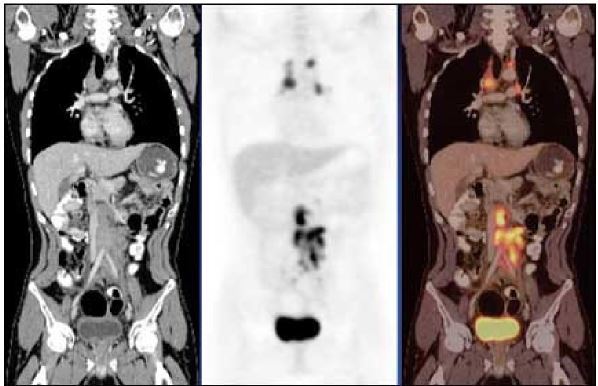

8

Q

imaging modality and orientation

A

-CT, PET, Fused

9

What is metabolized in PET scan?

Fluorodeoxyglucose (FDG) - metabolized like glucose; PET is map of glucose distribution in body

10

Why does bladder light up in PET scan?

normal, glucose is collecting there after being filtered out by kidneys